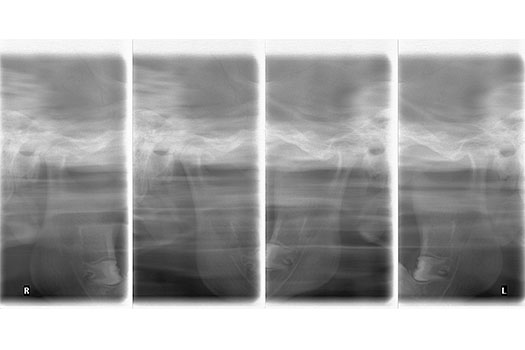

Usada por Rehabilitadores Orales, Cirujanos Maxilofaciales, Ortodoncistas. Permite determinar patologías a nivel de la articulación mandibular, esta se lo realiza a boca abierta y cerrada.